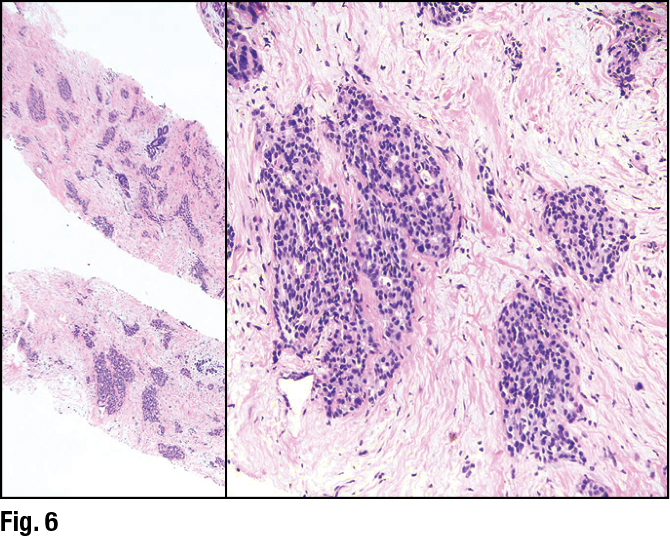

She showed an image of a lesion in a core needle biopsy that, in her view, looked like a grade two invasive ductal carcinoma (Fig. 6). “I think I would struggle to think this wasn’t a breast primary,” she said. The darker-appearing ducts in the left image are the normal terminal ductal lobular units. “The tumor cells are the larger nests of cells surrounding those ducts,” she said.

The ER stain was only weakly positive, however (Fig. 7), and she called this a point of caution. “If you have something that you think looks like a low- or intermediate-grade breast cancer, and the ER shows only weak positivity like this, you need to revisit your diagnosis because this should be strongly and diffusely ER positive.” In fact, the patient had a history of lung cancer and numerous lung nodules in addition to the breast mass.